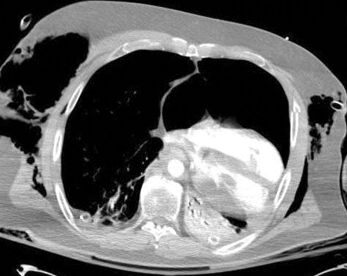

심장이 허니아?

사람 사진인데 이런 식으로 심장이 한쪽으로 너무 쏠려 있는, 다시 말해 종격동이 심장을 지지해주지 못하는 상태 수준으로 편위 되었을때 의심할만한 심낭을 통한 심장의 허니아 케이스가 보고되었다. 수의학에서는 첫 보고라고 하며 탐색적 개흉술 이전에는 진단하기 어려워 실제로 발생했지만 진단을 못했을 경우가 많았을것으로 보이니 기억해 둘것.

간단히 요약하면 심낭이 찢어져서 심장이 심남 밖으로 빠져 나온상태라는것.

| 개 한 마리가 교통사고로 인해 심장 탈장과 외상성 심낭 파열이 발생한 사례에 대한 보고입니다. 이 개는 사고 당시 심각한 흉부 외상이 의심되었음에도 불구하고 혈역학적으로 안정을 되찾았고, 우측 장골 골절을 교정하는 정형외과 수술을 받았습니다. 그러나 퇴원 후 실수로 떨어지면서 심한 호흡 곤란을 겪게 되어 12일 만에 재입원하게 되었습니다. 흉부 방사선 사진 상 심장 음영이 좌측 흉벽에 비정상적으로 위치해 있었고, 심한 종격동 편위가 관찰되었습니다. 환자의 호흡 상태가 위중하고 새로 발생한 기흉으로 인해 시험적 개흉술이 권고되었고, 수술 중 심낭의 완전 파열과 그로 인한 좌측 심장 탈출이 확인되었습니다. 그 외에도 흔한 흉부 손상들이 발견되어 부분적으로 교정되었습니다. 환자는 수술 후 4일 만에 회복되어 퇴원했습니다. 수의학 문헌상 외상성 심낭 파열과 심장 탈장이 보고된 것은 이번이 처음입니다. 사람의 경우에 따르면 이는 매우 드물고 치명적인 합병증으로, 수술 전이나 사망 전에 진단하기 매우 어렵습니다. 응급 수의사들은 둔상에 의한 흉부 외상 시 이러한 합병증이 발생할 수 있음을 인지해야 합니다. 본 증례에서는 발견되지 않았으나, 대혈관이나 심장 챔버의 감돈이 의심되거나 확인될 경우 수술적 치료가 필요할 수 있습니다. |